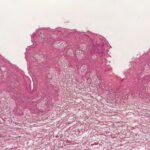

PATHOLOGY The intraepidermal adenocarcinoma of EMPD and MPD has a similar histologic appearance. There are groups, clusters, or single cells within the epidermis that show nuclear enlargement with atypia, prominent nucleoli, and well-defined ample cytoplasms . Intercellular bridges are absent. The cells can be within all levels of the epidermis and can compress but preserve the basal layer without junctional nest formation. The cells can extend into the contiguous epithelium of hair follicles and sweat gland ducts. Acanthosis, hyperkeratosis, and parakeratosis are often present. These cells have a “pagetoid” appearance and simulate other intraepidermal malignancies, including melanoma, pagetoid squamous cell carcinoma in situ, mycosis fungoides, cutaneous adnexal carcinomas (sebaceous carcinoma, porocarcinoma, and others), Merkel cell carcinoma, Langerhans cell histiocytosis, and other epidermotropic cutaneous metastases. The cells of MPD and EMPD can be pigmented, which should not necessarily indicate they are melanocytic. Paget's cells have intracellular mucopolysaccharides, with EMPD having a greater amount of mucin as compared

Immunohistochemistry is a useful adjunct in making the correct diagnosis. Low-molecular-weight cytokeratin stains cytokeratin 7 (CK7) and anti-cytokeratin (CAM 5.2) are sensitive markers for both MPD and EMPD . They are not completely specific, however, with both Toker and Merkel cells showing CK7 positivity. The cells of MPD and EMPD may stain with carcinoembryonic antigen and epithelial membrane antigen. The most useful keratin markers for Paget disease are CAM 5.2 and CK7, as they stain more than 90 percent of Paget's cells but do not react with epidermal or mucosal keratinocytes.13,14 The cells of pagetoid squamous cell carcinoma in situ typically do not stain with CK7 and CAM 5.2. S100 and HMB-45 are useful markers to exclude melanoma, as both are typically negative in MPD and EMPD. CK20 positivity has been found more frequently in cases of secondary EMPD with underlying carcinoma as compared to those cases of primary intraepithelial EMPD (CK7+/CK20-).15 Gross cystic disease fluid protein-15 (GCDFP-15) is a marker for apocrine epithelium and is typically positive in primary EMPD not associated with underlying neoplasm. In contrast, GCDFP-15 is frequently negative in those cases of secondary EMPD with an associated malignancy.16 Mucin core protein (MUC) expression is useful in the diagnosis of MPD and EMPD.17 MUC1 positivity is noted in both MPD and EMPD. MUC2 expression is generally negative in primary EMPD, but may be expressed in those cases of secondary EMPD with an associated underlying gastrointestinal adenocarcinoma. MUC5AC is frequently positive in primary EMPD and less commonly noted in secondary EMPD or those cases of primary intraepithelial EMPD that becomes invasive. SPECIAL TESTS Diagnosis of MPD and EMPD should be accompanied by a thorough search for underlying malignancy. Mammography is indicated in all cases of MPD, with biopsy of any underlying breast mass. In cases of EMPD, workup is directed toward the possibility of an underlying gastrointestinal or genitourinary neoplasm. Imaging of the abdomen and pelvis, colonoscopy, barium enema, cystoscopy, intravenous pyelogram, chest x-ray and mammogram (for the rare association of EMPD and MPD), and blood work are appropriate tests. Some reports have suggested that positron emission tomography scans may be useful for cases of invasive EMPD to evaluate for lymph node involvement and metastases. COMPLICATIONS Failure to identify and adequately treat cases of MPD can lead to metastatic disease with a poor prognosis. EMPD, if left untreated, can become invasive with a less favorable outcome. PROGNOSIS AND CLINICAL COURSE Overall survival in patients with MPD is affected by lymph node status and the presence of an underlying breast mass. Patients with negative lymph nodes have been shown to have a 10-year survival rate of 75 percent to 95 percent, whereas those with positive lymph nodes have a survival rate of 20 percent to 45 percent.4 Patients with a palpable breast mass have a 5-year survival probability of 35 percent to 51 percent, as compared to 75 percent to 82 percent in patients without a palpable mass. The prognosis for primary EMPD confined to the epidermis is excellent with appropriate treatment. Careful monitoring for early detection of local recurrence is critical given the multifocal pattern often present in EMPD. In contrast, invasive EMPD has a high rate of metastasis and carries a poor prognosis. The depth of invasion appears to be an important prognostic factor, with microscopic invasive disease (less than 1 mm) having a more favorable prognosis as compared to those with deeper invasion. Lymphovascular invasion and regional lymph node metastases markedly reduces overall survival rate and indicates a very poor prognosis. Clitoral EMPD has been shown to have a higher incidence of death from the disease as compared to other vulvar EMPD locations. In cases of secondary EMPD, the prognosis is related to the underlying carcinoma. TREATMENT Mammary Paget Disease Treatment of MPD is surgical. However, optimal surgical management of MPD remains to be defined, and treatment choice is frequently based on the presence or absence of an underlying breast mass. Mastectomy remains the standard definitive treatment. However, evidence suggests that MPD treated with breast-conserving surgery results in local control and survival rates similar to those achieved with mastectomy. Proper preoperative imaging is required to rule out multi-focal disease that would make breast-conserving therapy less effective and favor mastectomy. Lymph node evaluation via axillary dissection or sentinel lymph node biopsy must be considered in MPD. Adjuvant therapy with radiation, chemotherapy, or hormonal therapy is recommended based on lymph node status and specific features of the primary tumor. All diagnoses of MPD require referral to a physician with expertise in the management of breast cancer. Extramammary Paget Disease EMPD has been treated with a variety of different modalities. Although surgical management of the disease is the most frequently used method, various other treatments have a role for non-surgical candidates and as adjuvant therapy. SURGERY Surgery remains the treatment of choice for EMPD when tolerated by the patient. However, high local recurrence rates are seen after standard surgical excision, even with wide margins. This is most likely due to the irregular margins, multi-focal nature of the condition, and subclinical involvement of apparently unaffected skin. Several reviews have shown an overall recurrence rate of up to 44 percent with wide local excision, The local recurrence rates are higher in cases of invasive disease as compared to those limited to intraepithelial involvement. In addition, more radical and extensive surgeries are associated with lower rates of local recurrence. Patients with primary vulvar EMPD treated with radical vulvectomy, radical hemivulvectomy, and wide local excision have reported recurrence rates of 15 percent, 20 percent, and 43 percent, respectively. Multiple scouting biopsies to help delineate the extent of the disease before surgery can be a useful adjuvant technique.26 Intraoperative staining with CK7 is the preferred immunostain for intraoperative tissue evaluation.27 Sentinel lymph node biopsy has been described in the treatment of EMPD. Although this technique has been limited to a small number of reported patients and most cases of EMPD have in situ disease, sentinel lymph node biopsy may prove beneficial for those patients with increased risk of lymph node involvement and metastasis (i.e., dermal invasion of Paget's cells).29 MOHS MICROGRAPHIC SURGICAL EXCISION Given the high rates of local recurrence and the significant morbidity associated with radical and repeated surgeries, Mohs micrographic surgical excision (MMS) has been used to improve cure rates and for tissue sparing of critical genitourinary anatomic structures as compared to wide local excision.2,27,30,31 The recurrence rate after treatment with MMS has been reported as 16 percent for primary EMPD and 50 percent for recurrent EMPD. Ninety-seven percent of the cases treated with MMS required margins of 5 cm from the clinical tumor margin. However, if surgical margins of only 2 cm were used, as may be the case because wider margins may not be feasible when operating on the genitalia, only 59 percent of